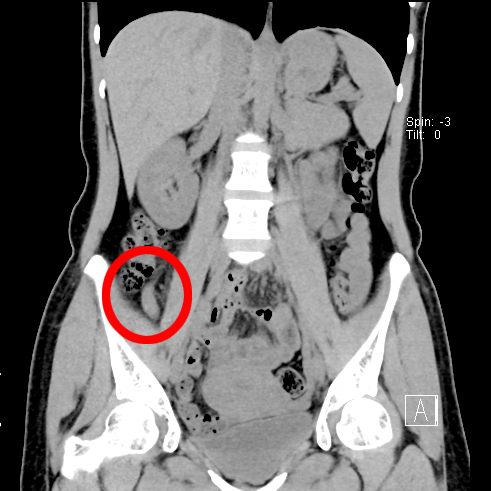

患者于3年前出现腹痛,以脐周及右下腹为主,疼痛反复发作,药物治疗后均无明显改善,辗转多家医院就诊,大大影响了患者的生活质量。近日患者来到我院脾胃肝胆科主任徐宏伟教授门诊就诊,徐宏伟主任结合患者的体征和CT检查结果,诊断为慢性阑尾炎。

术中利用无痛肠镜技术到达阑尾开口,采用最新的“eyeMAX洞察”子母镜系统直视下进入阑尾腔内,通过冲洗、引流、网篮套取等操作,将嵌顿于阑尾腔内的粪石取出,术后患者腹痛明显缓解,1h后即可下地行走。次日顺利出院。